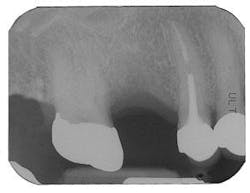

Figure 8 - Healed bone graft Tooth No. 3

Figure 9 - ITI implant placement Tooth No. 3